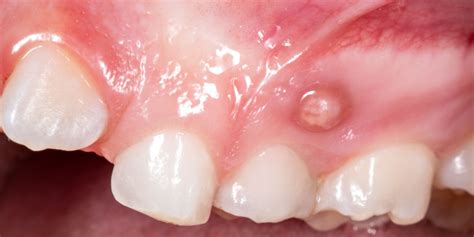

Una fístula dental es una afección oral que implica la formación de un conducto anormal entre el diente y el exterior de la boca. Una fístula dental es una pequeña abertura o canal anormal que se forma en la encía o en la región cercana a la raíz de un diente infectado. Una fístula es un canal anormal, formado entre dos órganos o entre un órgano y la superficie corporal. Cuando hablamos de una fístula de carácter dental, se refiere a la aparición de un canal que conecta algún tejido blando de la boca (encías, paladar blando, lengua, piso de la boca, labios, área periapical y región submandibular.) con superficies de la mucosa oral (superficie de las encías, superficie interna de los labios y de las mejillas, el paladar duro y blando, superficie de la lengua y el tejido bajo la lengua.), como el resultado de una infección desatendida, que se expandió desde los tejidos internos, hacia la salida exterior más próxima, para drenar el pus. La fístula dental tiene el aspecto de una ampolla llena de pus en la boca, similar a un grano de pus.

Una fístula dental es un pequeño bulto que aparece en la encía o el paladar como consecuencia de una infección oral. Con menos frecuencia, también puede surgir en la cara o el cuello. Asimismo, se caracteriza por la supuración de pus. Por último, puede ir acompañada de dolor o fiebre.

Un absceso dental es una acumulación de pus causada por una infección bacteriana en el tejido dental. En el caso de una fístula dental, el absceso puede manifestarse como una protuberancia roja y dolorosa en las encías cerca del diente afectado. Esta protuberancia puede estar acompañada de sensibilidad al tacto y al calor, así como de hinchazón en el área circundante.

Cuando se forma la fístula dental, aún no causa dolor. Al principio, la zona afectada se hincha. Las encías se enrojecen y hay una sensación de tensión en el diente. A continuación, se forma una ampolla en la encía, encima o debajo del diente afectado, que se llena de pus a medida que avanza. La fístula dental empieza a palpitar y doler. Puede que incluso se te hinche la cara del lado afectado y te duela la cabeza.